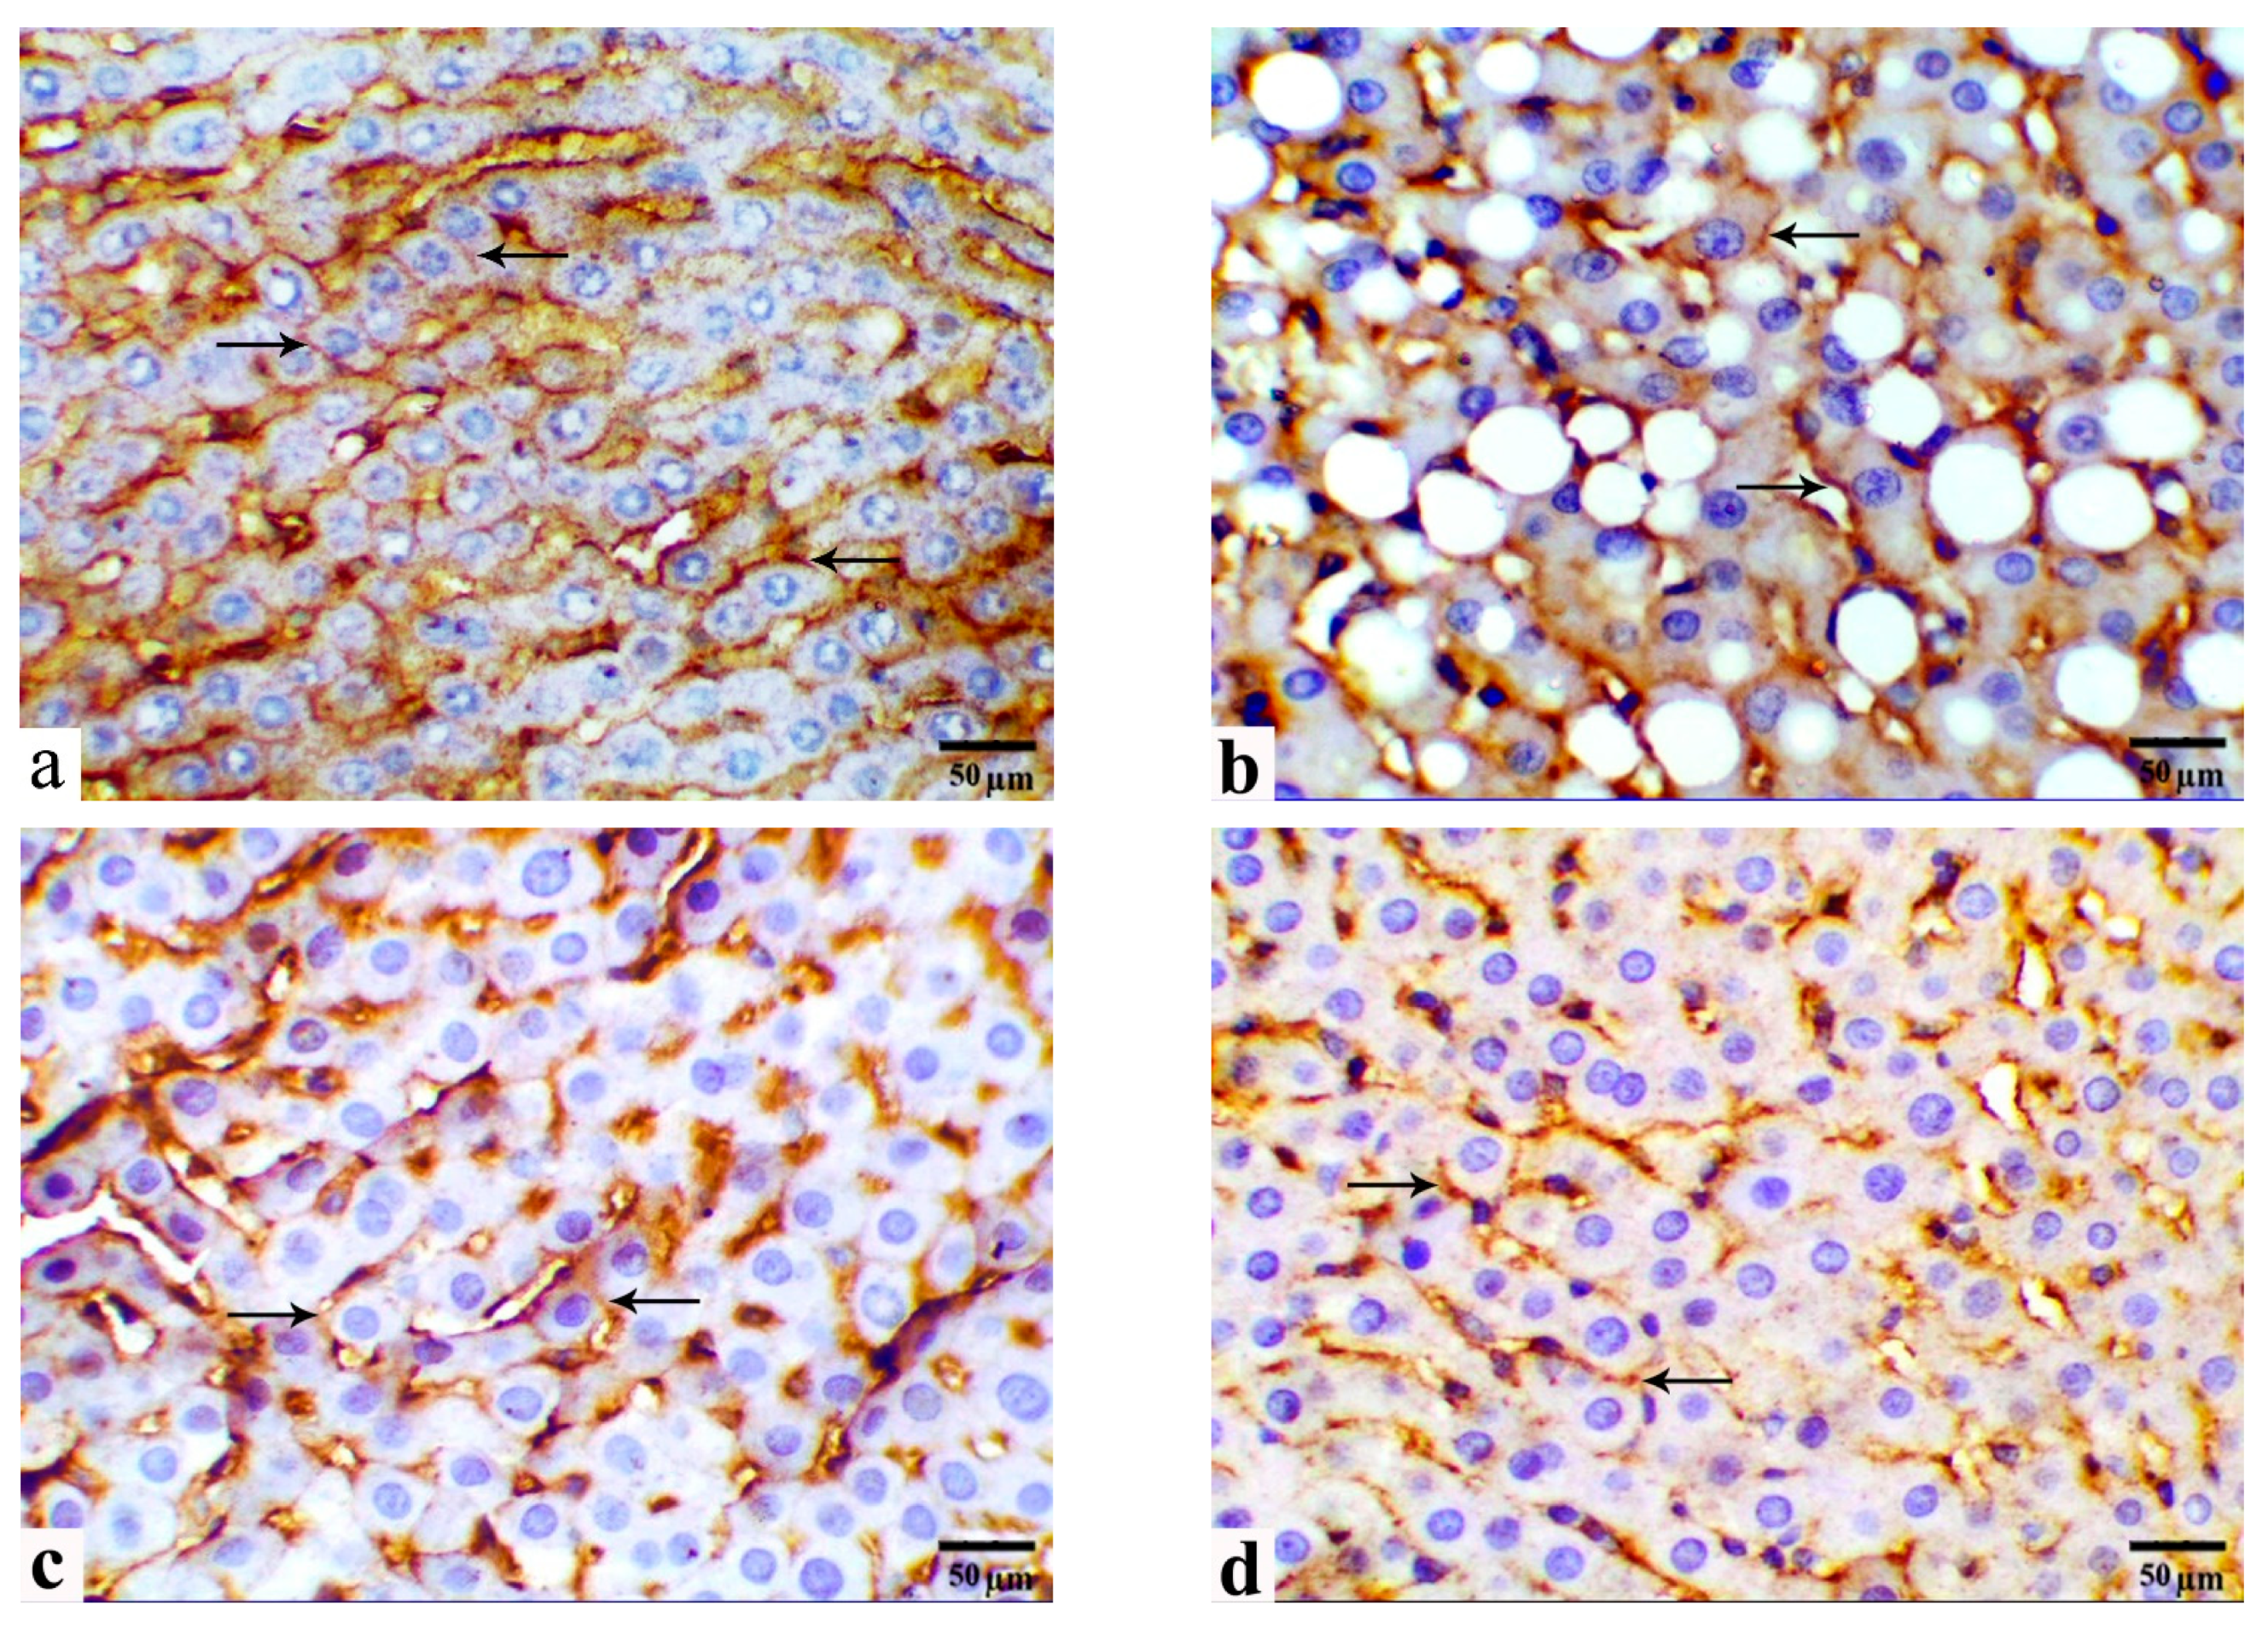

3.5. Immunohistochemical Observations